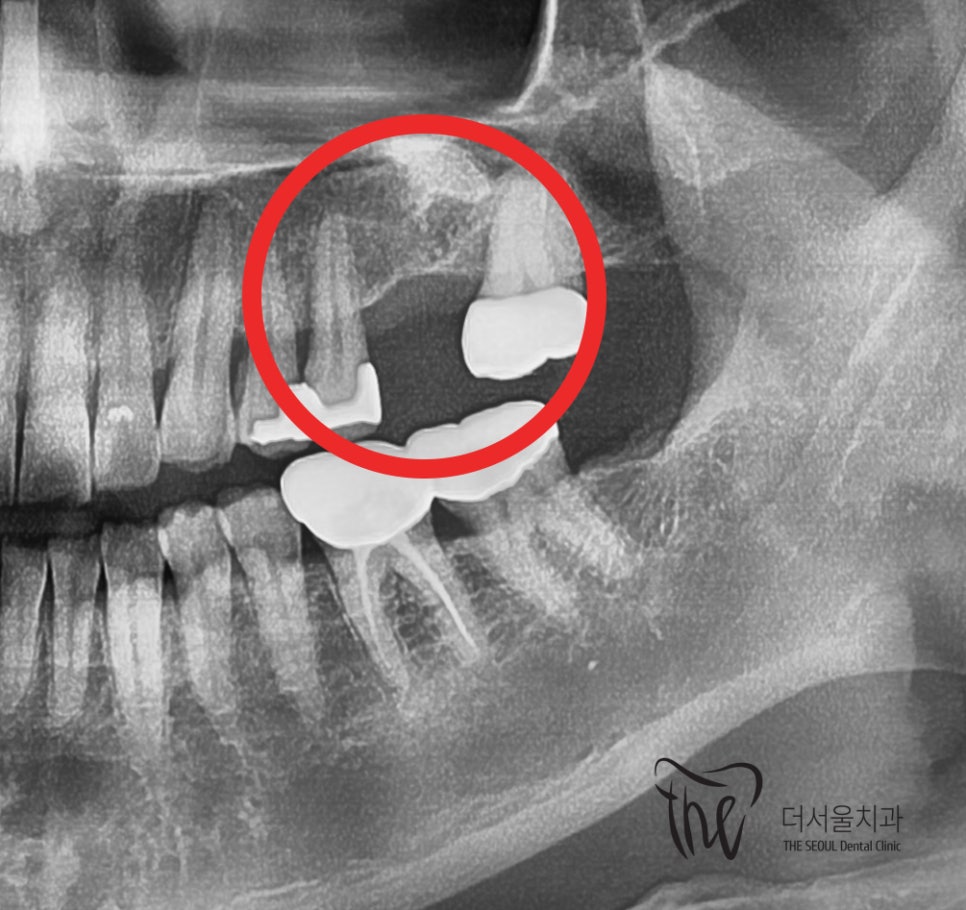

처음에 오셨을 때, 과거에 시술 받았던 곳이

시큰거리다는 느낌으로 찾아오셨었는데

손으로 만져봤을 때, 별 다른 특이사항이 없었으며

엑스레이를 찍어서 봤을 때 또한 주위에

뼈가 녹아있는다던지 하는 등의 이상 소견은

눈에 띄지 않았었습니다.

이상하죠?

근데, 손으로 만져봤을 때는 임플란트 흔들림 이

느껴졌기 때문에 좋지 않은 상황이라는 것을

그제서야 알 수 있었습니다.

근데, 혹여나 하는 마음에 단순히 어버트먼트 나사가

흔들리는 것이 아닐까? 라는 생각을 가졌었으나..

그건 아니였었습니다.